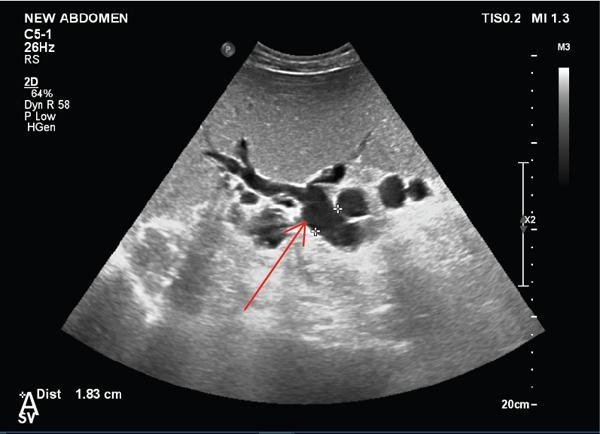

Shrinivas B. Desai, Ritu K. Kashikar, Aman Snehil, Ajay Jhaveri Cirrhosis is a late stage of irreversible scarring of the liver causing abnormality in liver structure and function. Multiple conditions and factors can cause repeated liver damage and scarring ultimately leading to cirrhosis. The most feared complication of liver cirrhosis is the development of hepatocellular carcinoma (HCC). Portal hypertension (PHT) is seen with a variety of conditions but cirrhosis happens to the most important cause. Imaging plays a vital role in noninvasive diagnosis and treatment planning of both cirrhosis and PHT. Liver imaging reporting and data system (LI-RADS) is a standardized reporting system assigning an observation risk of representing HCC. This chapter focuses on discussing aetiologies and imaging of PHT with a lucid review of L1-RADS 2018 version. The portal blood circulation is a unique circulatory circuit as it connects two capillary beds between the liver parenchyma at one end and the gastrointestinal tract and splenic parenchyma at the other end. The portal system ramifies in the liver and ultimately ends in the hepatic sinusoids from where the blood ultimately drains into the inferior vena cava (IVC). The portal vein (PV) originates from the capillary beds in the stomach, intestine and the spleen. The main PV is formed behind the neck of the pancreas by the confluence of the superior mesenteric vein (SMV) and splenic vein. It continues to the porta hepatis where it bifurcates into the left and right branches as it carries nutrient rich but oxygen poor blood to the liver (Fig. 9.9.1). The PV makes up for 75%–80% of the liver’s blood supply while the hepatic artery which arises from the celiac trunk makes up for the remaining 25%. A pathological increase in the portal venous pressure is referred to as PHT. PHT is most often a sequel of chronic parenchymal liver disease and leads to major life-threatening complications due to bleeding from the collateral circulation (most commonly oesophageal varices). Direct measurement of portal pressure (PP) is invasive and often not feasible in most patients and thus imaging plays an important role in the diagnosis of PHT and its complications. The normal portal venous pressure ranges between 5 and 10 mmHg, which is the equivalent of 7–14 cm H2O. The normal hepatic venous pressure gradient (HVPG) is the pressure gradient between the PV and the IVC, is typically 1–5 mmHg. Presence of PHT is indicated by a wedged hepatic venous pressure of more than 5 mmHg. Other definitions include a splenic pressure of more than 15 mmHg or an intraoperative PP of greater than 30 cm H2O. The complications of PHT are seen when HVPG is greater than 10 mmHg and hence this value defines clinically significant PHT. Variceal bleeding is seen with a pressure greater than 12 mmHg. In ideal conditions, the portal circuit is a high flow, low resistance circuit as it has to allow substantial flow rates of 700–1000 mL/min to the hepatic parenchyma from the gastrointestinal tract. Anatomical changes in the organization of the hepatic lobule can result in rise in the portal resistance. These can occur in the form of collagen deposition in the space of Disse, fibrotic scars formed due to regenerative nodule (RN) formation, loss of normal elasticity of the endothelium and distal venous thrombosis. Changes in splanchnic haemodynamics due to factors that increase splanchnic blood flow and increase in intrahepatic vascular resistance due to transformation of stellate cells into myofibroblasts also contribute to the increase in PP gradient. In Western countries, alcoholic cirrhosis and viral cirrhosis are the leading causes of PHT and oesophageal varices. The viral causes form majority of cases leading to cirrhosis and PHT in the Far East and Middle Eastern countries while Schistosomiasis remains an important cause in the African countries. Worldwide, nonalcoholic steatohepatitis (NASH) and hepatitis C are the emerging causes of chronic liver disease (CLD) and PHT. PHT can be classified as cirrhotic and noncirrhotic depending on whether it is associated with cirrhosis or not. This distinction is important as noncirrhotic causes like PV thrombosis are at high risk of development of bleeding but tend to have a better chance of surviving a variceal bleed than a patient with decompensated alcoholic cirrhosis due to preserved hepatic synthetic functions in the former. PHT can also be classified on the basis of the location of the pathology into prehepatic, hepatic and posthepatic causes. Hepatic causes can further be divided into presinusoidal, sinusoidal and postsinusoidal. The causes of portal hypertension have been denoted in Table 9.9.1. The direct measurement of the PP by measuring the HVPG is invasive, expensive not readily available in all patients. Thus, imaging plays an important role in the diagnosis of PHT. Various modalities are used for the imaging diagnosis of PHT. Ultrasonography (USG) and Doppler evaluation have the advantage of being inexpensive, readily available and bedside modality (Table 9.9.2). The role of ultrasound and Doppler in imaging of PHT is to: Grey scale imaging is useful in evaluating the splenoportal anatomy. The evaluation should begin with the liver morphology. Signs of cirrhosis like nodularity of the liver surface with relative atrophy of the right lobe and prominence of the left lobe and caudate should be looked for. Hepatic echotexture appears coarse and more echogenic (Table 9.9.3). Increase in portal venous diameter is a sign of PHT (Fig. 9.9.2). Portal venous diameter of more than 13 or 15 mm has low sensitivity for diagnosing PHT of only 40%–12.5%, respectively. Absolute measurement of the portal diameter as a sign of PHT is also fallacious as in presence of collateral circulation or hepatofugal flow; there may actually be a decrease in the PV diameter. Therefore, a more accurate sign is respiratory variation of PV diameter. An increase in PV diameter of less than 20% with deep inspiration has been reported to indicate PHT with a sensitivity of 80% and specificity of 100%. This has been reported to be an accurate indicator of cirrhosis. Hepatic vein straightness, uniformity of vein wall echogenicity and visualization of at least 1 cm segment of the hepatic vein are the parameters used for evaluation. Splenomegaly is defined as bipolar splenic diameter of greater than 12 cm or largest splenic cross-sectional area passing through the hilum of greater than 45 cm2, and occurs secondary to PHT (Fig. 9.9.3). A total of 65%–80% patients with cirrhosis have splenomegaly on ultrasound. Patients with cirrhosis due to viral hepatitis and primary biliary cirrhosis show splenomegaly more frequently than those with alcoholic cirrhosis. This is an accurate sign of PHT. USG is extremely sensitive with respect to detecting subclinical ascites. Perihepatic space is the most usual site of visualization of minimal ascites. In normal subjects, this ratio is approximately 0.07 and a value above 0.1 suggests the diagnosis of PHT with a 95% sensitivity and specificity. The normal spectral waveform of the hepatic artery is a low resistance flow pattern with forward flow in diastole and a resistivity index in the range of 0.5–0.7. In PHT, the resistivity index of the hepatic artery increases with high resistance flow pattern due to increased peripheral vascular resistance. Resistance index (RI) > 0.78 in the intrahepatic branches of the hepatic artery has been reported to have a sensitivity of 50% and a specificity of 100% for the detection of PHT (Fig. 9.9.11). Pulsatility index (PI) > 1.05 suggests severe PHT with a sensitivity of 86% and specificity of 88% (Fig. 9.9.11). Patency of hepatic veins should be evaluated to rule out Budd–Chiari syndrome as a cause of PHT. The normal hepatic venous waveform (HVW) reflects right atrial activity and this results in a triphasic waveform with one positive and two negative waves. In PHT, this waveform becomes monophasic or biphasic. A monophasic HVW has a sensitivity and specificity of 74% and 95%, respectively, in the diagnosis of severe PHT (Fig. 9.9.12). Dilatation of the splanchnic veins – the SMV and the splenic vein – more than 11 mm are suggestive of PHT with a sensitivity and specificity of 72% and 100%, respectively. A reduction in the respiratory variation of the splenic vein and SMV to less than 40% had a sensitivity and specificity of 79.7% and 100%, respectively, for the diagnosis of PHT (Fig. 9.9.13). The splenic artery reveals an increase in the resistivity index and an RI of >0.63 and a PI of >1 have a sensitivity and specificity of 84.6% and 70.4% for the diagnosis of PHT. Presence of portosystemic collaterals like patent paraumbilical vein, dilated left gastric and short gastric veins are 100% specific sign for PHT (Figs. 9.9.14–9.9.16). Recanalization of the paraumbilical vein, known as the Cruveilhier–Baumgarten syndrome is observed in 43% of patients with PHT, and this is the easiest collateral to assess during the US examination. Various portosystemic collaterals that occur in PHT have been discussed in details in subsection on CT findings in PHT. No Doppler parameter is considered reliable enough to measure PP with sufficient accuracy for use in clinical practice. Oesophageal varices are often present in patients with portosystemic collaterals. Appearance or increase in number of collaterals along with splenomegaly has a high association with variceal formation and growth. USG helps in diagnosis of prehepatic causes like portal stenosis or thrombosis by demonstrating the patency and morphology of the splenoportal system. Arteriovenous fistulae and tumours causing vascular thrombosis as aetiology can be readily detected. USG helps in diagnosis of features of cirrhosis and thus helps differentiate noncirrhotic causes of PHT. USG allows diagnosis of fatty liver disease, which is an emerging cause of cirrhosis. Among the posthepatic causes, USG aids in establishing the diagnosis of Budd–Chiari syndrome by demonstrating the patency and morphology of the IVC and hepatic veins. Owing to the inability of CT to detect flow direction, portal flow rates or pressure gradients, CT is not the primary modality in diagnosis of PHT. Similar to USG dilatation of portosystemic system is a feature of PHT (Fig. 9.9.17). Changes in cirrhosis if present can be seen in the form of surface nodularity, nodules and fibrous septae. CT plays an important role in diagnosis of portal venous thrombosis and evaluating its extent. An acute thrombus is seen as a hypodense filling defect in the vessel causing distension of the venous lumen. Surrounding fat stranding can be seen. A chronic thrombus appears as an eccentric filling defect usually along the wall and is often associated with decrease in vessel diameter. Calcification may be seen in chronic thrombi. Multidetector computed tomography (MDCT) is a useful tool to evaluate portosystemic collateral circulation and recognize complications of PHT. 3D angiography can help understand portal venous and complex variceal anatomy and plan treatment. The various portosystemic collaterals are discussed below. They can be classified into those draining into superior vena cava (SVC) and those draining into the IVC. Magnetic resonance imaging (MRI) is a noninvasive modality used in the evaluation of PHT without the use of ionising radiation. It provides evaluation of parenchymal abnormalities, collaterals and characterization of tumours (Fig. 9.9.28). Spin echo sequences allow characterization of liver masses and liver parenchyma. Loss of flow void allows for detection of thrombosis. Time-of-flight (TOF) angiography is useful in assessing the portal venous system and allows for successful detection of PV thrombosis. The disadvantages of TOF are motion artefacts caused by breathing, long acquisition times and incomplete coverage of the portal venous system. Novel imaging techniques include phase contrast, T1 mapping and magnetic resonance elastography (MRE). The advantage of phase contrast over TOF imaging is that phase contrast imaging acquires information regarding the flow direction in addition to the information regarding the flow velocity. On-phase contrast images signal within vessel is hyperintense when flow is cranial and hypointense when flow is caudal. Look-Locker imaging technique using gradient echo (GRE) MRI sequences with inversion recovery pulse is used to quantify fibrosis by measuring precontrast T1 relaxation times. Interventions in PHT can be aimed at diagnosis or more commonly at management of complications of PHT. HVPG measurement, which is the gold standard for the diagnosis of PHT, can be achieved through cannulation of the PV. Transjugular hepatic biopsy is another diagnostic invasive technique that also allows indirect measurement of PP. Disadvantages include deterioration of hepatic function caused by diversion of portal venous blood flow and shunt dysfunction. TIPSS is contraindicated in patients with congestive heart failure, severe pulmonary hypertension, severe tricuspid regurgitation and hepatic failure. In this technique, a catheter is advanced from the femoral vein into the outlet of the gastrorenal, usually in the region of the left renal vein. The shunt is then occluded with a balloon and sclerosant is injected retrograde to occlude the gastric varices. Histological development of RNs surrounded by fibrous septae in response to chronic liver injury, progressing PHT and end-stage liver disease is termed as cirrhosis. Although initially considered an end-stage phenomenon in CLD, recent evidence suggests that the histological fibrosis can be reversible in early stages with the initiation of specific therapies, for example, in viral cirrhosis with the initiation of antiviral therapy. The one-year mortality rate in cirrhosis varies widely from 1% to 57% depending on the occurrence of complications. Cirrhosis can have a wide variety of causes ranging from congenital to acquired and infectious to noninfectious. It is also a major aetiologic risk factor for the development of HCC. Imaging plays an important role in aetiologic diagnosis of this diverse entity as well as in the diagnosis and management of its complication and surveillance for oncological transformation.

1. Portal vein diameter

F. Portosystemic collateral channels (Table 9.9.5)